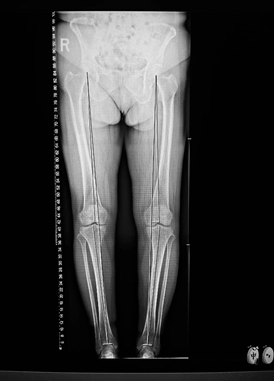

患者酷爱运动,因“O型腿”,膝关节内侧疼痛难忍就诊,新院区骨科关节组医师团队深入践行个性化治疗理念:每位患者的年龄、职业、活动需求、病变程度都独一无二,要为其“量体裁衣”,制定最佳方案。经过细致的影像学评估和数据分析,团队发现该患者病变仅局限于膝关节内侧间室,外侧软骨和韧带功能良好,完全符合HTO手术的“精准适应证”。术前,团队利用数字化技术进行了精确的截骨模拟和力线规划,确保了手术方案的“毫米级”精准度。

手术中,关节组医师团队凭借精湛技艺,犹如一位“骨骼工程师”,精确地调整了患者的下肢力线,将压力从磨损的内侧成功转移至健康的外侧。术后患者膝关节疼痛症状迅速缓解,并于次日开启康复训练,重燃运动希望。